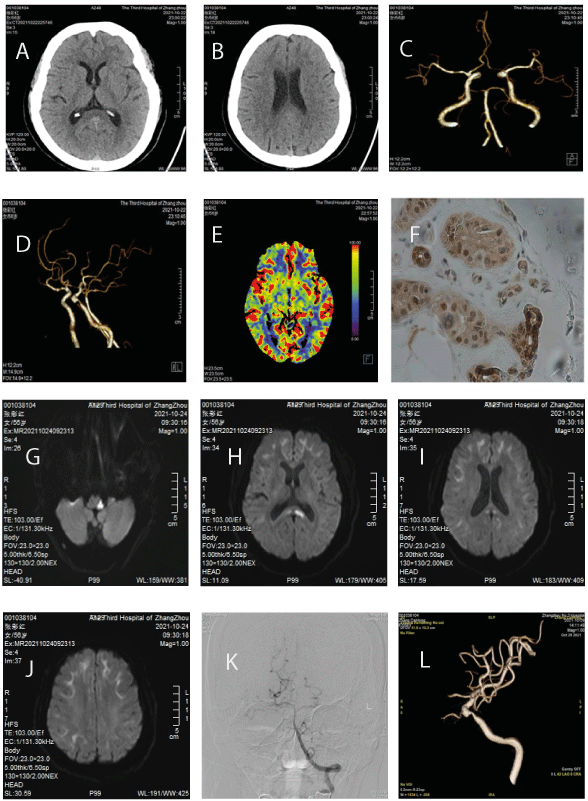

On the same day a brain computed tomography (CT) scan showed there wasn't obvious abnormality (Figure 1, A-B). Computed tomography angiography (CTA) of the head and neck showed severe stenosis of the left internal carotid artery (ICA)-C6 segment (Figure 1C), and mild stenosis of the right middle cerebral artery (MCA)-M1 segment (Figure 1D). No obvious abnormality was observed in computed tomography perfusion (Figure 1E).

Figure 1. Brain CT scan: A-B, CTA: C-D, CTP: E, Skin biopsy: F, brain MRI: G-J, DSA: K-L

On the third day, brain MRI showed AIS at tubera corporis callosi and left Wallenberg (Figure 1, G-H), and hyperintensity in the corticomedullary junction on diffusion weighted image (DWI) (Figure 1, I-J). The electrocardiogram and echocardiography were normal. Ultrasound examination revealed fatty liver.

One week after hospitalization, digital subtraction angiography (DSA) examination revealed bilateral posterior communicating arteries are absent (Figure 1K), and severe stenosis of the left internal carotid artery (ICA)-C6 segment (Figure 1L).

Skin biopsy showed eosinophilic ubiquitin-positive and P62-positive intranuclear inclusions in adipocytes, fibroblasts and sweat gland cells (Figure 1F).